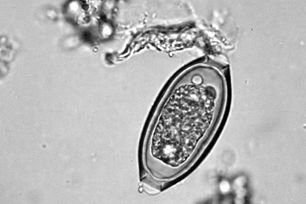

Infectious disease | Parasitology

Fecal Dx antigen testing

Detects up to 2x more intestinal parasite infections than fecal ova and parasites testing alone.

Fecal

Our tests can detect more types of parasites earlier than ever, without the presence of eggs, even in well dogs and cats. Even prepatent and single-sex infections can’t hide.